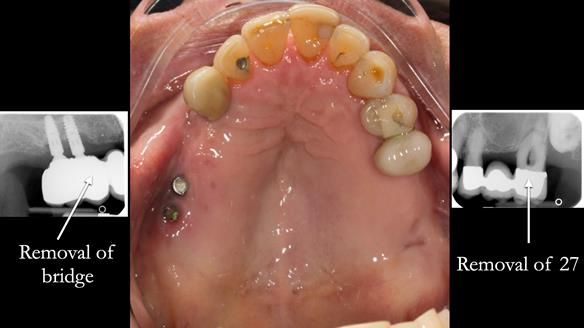

In the upper arch:

- a failing upper left tooth supporting a bridge was removed

- an implant-supported bridge on the upper right was dismantled

A metal-based upper RPD was made,

with metal backings incorporated to future-proof the design

should further teeth fail.

It also shows how an upper right bridge was converted into an implant-supported denture, using a conveniently placed implant in the 17 region, converted from a bridge to a Locator attachment.

Ken’s implant system was Nobel Biocare, and the case highlights how thoughtful planning can turn a problem into a long-term advantage.